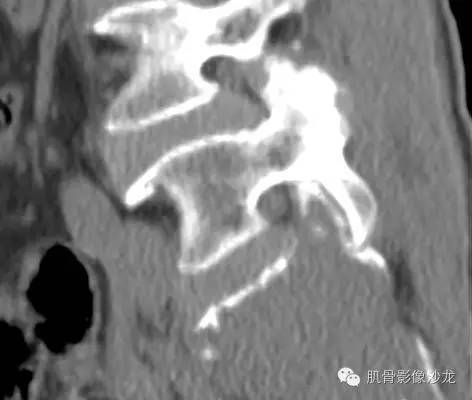

女,50岁,腰痛伴左下肢放射痛4个月

骶骨巨大骨质破坏区,破坏区软组织肿块密度较均匀,边缘不规则残留少许骨皮质,膨胀性改变不明显,肿块基本局限于骨破坏区内。

最后病理:高分化浆细胞瘤

这个溶骨性骨质破坏征象,骶骨的形态还是保留的 所以影像也像浆细胞瘤 但是 转移瘤必须鉴别 转移瘤万能的模仿者